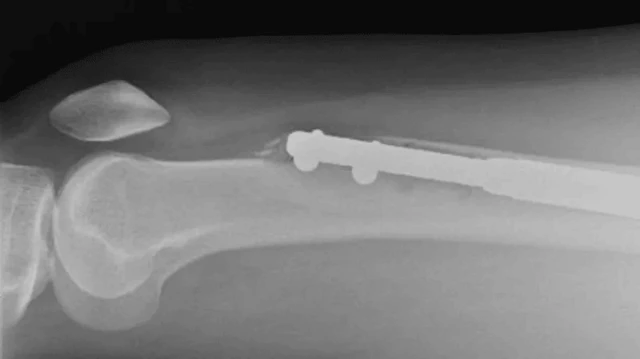

Kwa operesheni hii, maumivu fulani yanatarajiwa. Ni operesheni ambayo mifupa ya mguu imevunjwa mara mbili na fimbo ya chuma imewekwa ndani.

Fimbo za chuma huongezwa urefu hatua kwa hatua ili kuongeza urefu wa mguu na kutengenisha nusu mbili za mfupa. Mifupa iliyokatwa hupona hatua kwa hatua, ili kujaza pengo la kati.

Elaine alikwenda kufanyiwa uchunguzi, ambao ulithibitisha hofu yake. Msumari wa mguu wake wa kushoto ulikuwa umekatika kwenye fupa la paja. Alifadhaika, lakini anasema aliambiwa asiwe na wasiwasi na Dk Guichet.

"Daktari Guichet aliniambia msumari ulikuwa umekatika alipokuwa akiutoa."